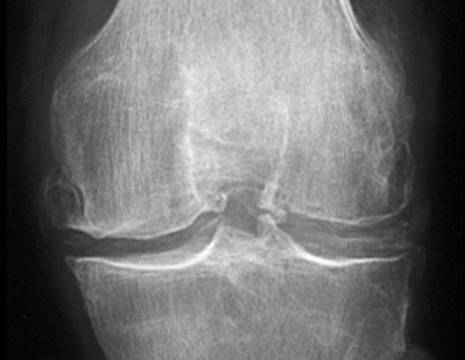

Artrosi, ginocchio

Artrosi ed artrite al ginocchio

L'artrosi di ginocchio è una lenta e progressiva malattia degenerativa, in cui la cartilagine articolare si usura poco a poco.

GINOCCHIO NORMALE E CON ARTROSI

Più spesso colpisce le persone anziane, ma può colpire i pazienti più giovani, soprattutto quelli con pregresse lesioni ai menischi, alla cartilagine od ai legamenti.